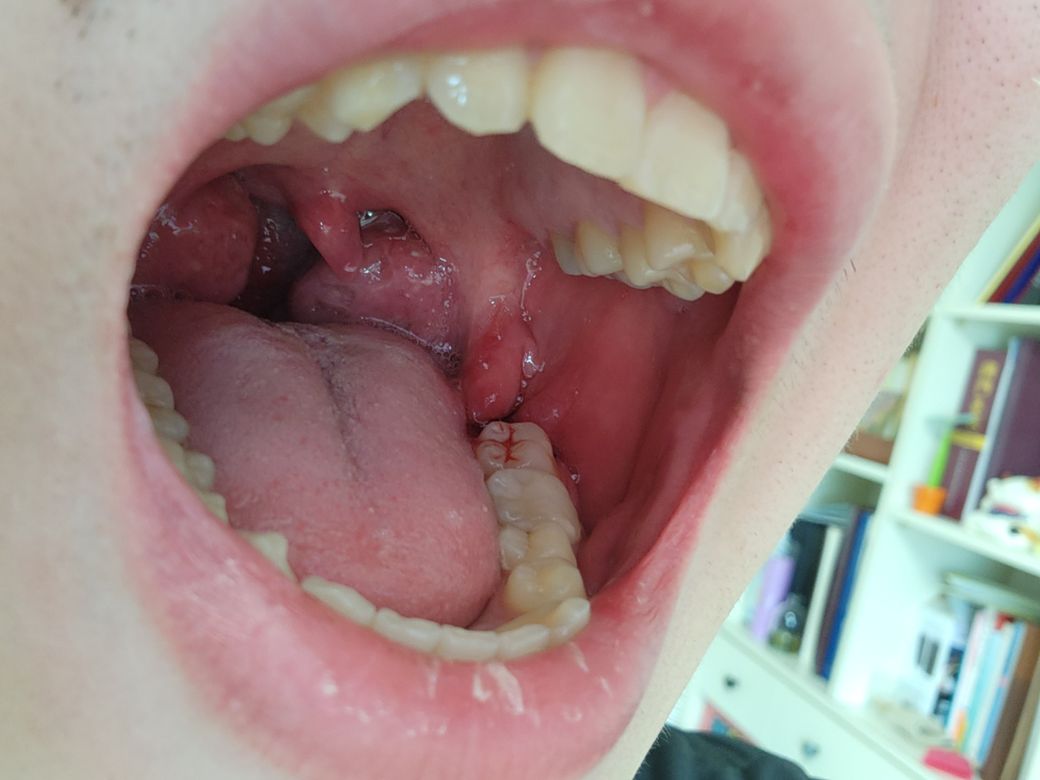

사랑니 이 정도면 지혈이 거의 다 되었다고 봐도 무방한가요?

오늘 10시 40분쯤에 발치는 끝났고 거즈를 꽉 물고 있다가 12시 38분쯤인가 뺐다가 한 5분뒤에 다시 물고 한 10분뒤에 마취가 풀려서 통증때문에 물기가 힘들어서 지금은 거즈가 없는 상태입니다. 혹시 다시 거즈를 물어야 하나요? 혀에 피 맛은 살짝 느껴집니다. 그리고 욱신거리는 거는 약 먹으면 가라앉겠죠?

저정도면 피가 아직스믈스믈 나오는 상태입니다. 거즈를 더 물고 계시는게 좋을것같습니다. 약을 드시면 통증은 괜찮아 지실꺼에요.

현재 상태에서는 더이상거즈를 물지 않아도 되며 스며나오는 피의 경우 벧어내지 말고 삼키길 권합니다.